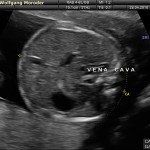

A fianco alla più tradizionale ecografia eseguita per via transaddominale, risulta particolarmente utile nell’esame ecografico ostetrico e ginecologico la via di accesso transvaginale.

Con questa metodica, utilizzando delle sonde ecografiche appositamente predisposte (per forma e dimensione, e per frequenza di emissione degli ultrasuoni) è possibile controllare la gravidanza nel primo trimestre con una qualità e definizione d’ immagine nettamente superiori a quanto possibile per via transaddominale.

Per eseguire l’ecografia transvaginale non è richiesta la vescica piena, diversamente rispetto a quanto richiesto per l’ecografia transaddominale. L’approccio transvaginale consente di aggirare l’ostacolo dovuto ad un aumentato spessore della parete addominale (obesità). In questi casi infatti la qualità d’ immagine in caso di ecografia transaddominale viene fortemente penalizzata dall’eccessivo spessore del pannicolo adiposo addominale.